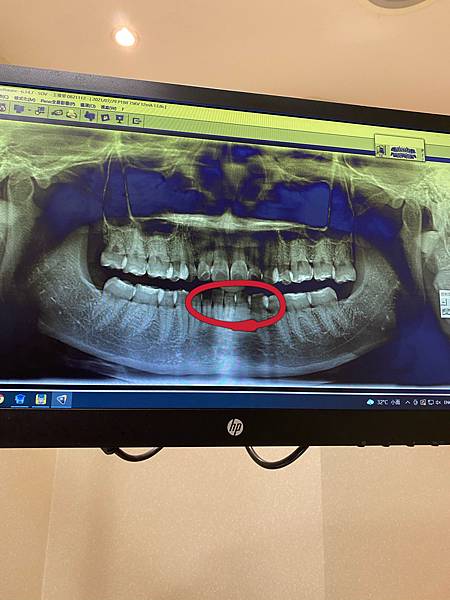

自從我拍了一個超特寫的廣告,我的下排牙齒被放大到超特寫,所以牙齒一整個看起來超歪斜,雖然之前有做過矯正,但之前就是沒有好好戴維持器,結果下排一整個大亂 其實也有想過要做二次矯正,但之前已經燒了一波錢了!所以費用也是我一直在考慮的問題,不過最近剛好朋友在做隱形矯正,接觸到

SMILUX樂齒微矯正,專門就是為我這種想要二次矯正,或是兔寶寶牙、齒縫過大、牙齒有點亂,還有我這種下排門牙歪斜的人設計的,可以集中矯正前排牙齒, 重點是微矯正專案價只要99,000

元,不拔牙一年內就可以矯正完成 沒想到可以不用花很長的時間,還有很貴的費用就可以做透明矯正,所以立馬預約來評估看看,這次預約的是日亞美牙醫的吳醫師,診所環境一整個很舒適,很喜歡這種像家的感覺